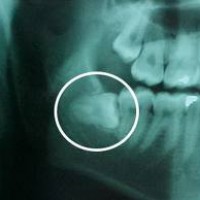

Răng khôn là chiếc răng mọc sau cùng (mọc vào khoảng từ 18 đến 25 tuổi). Khi 28 chiếc thông thường đã mọc đủ trên cung hàm rồi, nếu còn chỗ thì 4 chiếc răng cuối cùng này sẽ được mọc lên ngay thẳng cùng các răng khác

Nhiều nha sĩ khuyên nên nhổ các răng ngầm, là răng mà chỉ có một phần được mọc nhú lên. Vi khuẩn có thể xâm nhập vào vùng xung quanh của răng nhú lên một phần này và gây nhiễm trùng, nhiễm trùng có thể lan xuống vùng xương xung quanh và